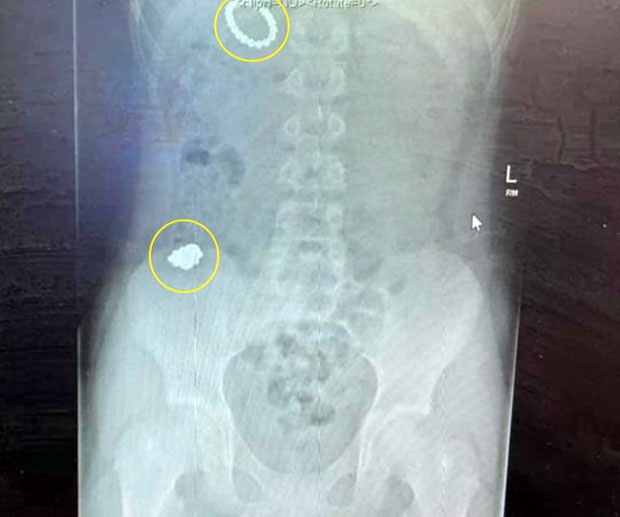

영국 그레이터맨체스터 프레스트위치에 사는 라일리 모리슨(12)은 지난달 스스로 ‘자석맨’이 되기 위한 실험을 감행했다. 자석을 삼키면 인체도 자석처럼 물체를 끌어당기는 자성(磁氣)을 갖게 되는지 알아내는 게 목표였다. 실험에 돌입한 소년은 1월 1일 새해가 되자마자 자석 한 묶음을 삼키곤 배에 금속이 붙는지 확인했다. 아무런 효과가 없자 소년은 사흘 뒤 다시 한 묶음을 입에 넣었다.

자석을 두 개 이상 삼키면 몸 안으로 들어간 자석이 장내에서 서로를 끌어당겨 천공과 패혈증을 유발할 수 있다. 심하면 사망에 이른다. 소년을 치료한 의료진은 “자석을 삼키는 아이가 많은 데 이는 매우 위험하다. 예전에 어떤 아이는 장 일부를 제거해야 했다. 소년은 자석 54개를 삼킨 것 치고 운이 좋았다”며 부모의 관리를 당부했다.